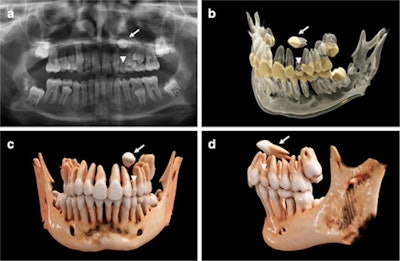

In the report, researchers used cinematic rendering for the volumetric image visualization of midface CT datasets. Predefined reconstruction parameters were specifically modified to visualize complex orthodontic cases in children with ectopic, impacted, and supernumerary teeth. Using the masking and windowing functionality of Siemens Healthineers' Cinematic Anatomy application, upper and lower jaw and respective dentitions were easily segmented, creating natural-appearing images for realistic representations of anatomy, the authors wrote.

"(Nevertheless,) the 3D spatial relationship of the teeth, as well as their structural relationship with the antagonizing dentition, could immediately be investigated and highlighted by separate, interactive 3D visualization after segmentation through windowing," Willershausen and colleagues wrote.